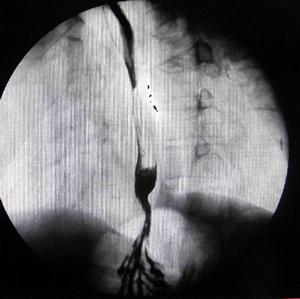

食管裂孔疝X線鋇劑造影:

胃黏膜呈幕狀牽引食管裂孔疝X線鋇劑造影:膈上見胃囊食管裂孔疝 X線鋇餐造影:Schatzki環上移,胃黏膜上牽內腔鏡是診斷食管裂孔疝僅次於放射學檢查的方法。纖維胃鏡較金屬硬管鏡檢查時安全、痛苦小,並可同時檢查胃和十二指腸,以排除引起胃壓升高的因素,且可多次使用,檢查方便。如有裂孔疝時可見食管下括約肌鬆弛,呼氣和吸氣時均呈開放狀態。正常情況下吸氣時食管胃交界點下降,如有疝則不變位,食管鏡內出現胃液的水平較正常時高。如為返流性食管炎時,通過胃鏡可觀察到紅斑、潰瘍的數目、嘗試及其排列情況,潰瘍出血,黏膜糜料及縮穿等。如果經過呼吸周期而賁門呈開放狀,這是返流的另一指征。如病人主訴主要是吞咽困難,套用於“丁”字手法,從下面觀察賁門,也許可以排除早期癌在此區的存在,將胃鏡後退到食管。細心地逐步檢查十分重要。如發現食管縮窄及嚴重食管炎,或懷疑有Barrett柱狀上皮,應作多處活檢,食管潰瘍也可以發生惡性變。當不能排除癌,則使用金屬硬鏡作深部活檢以明確診斷。對某些食管縮窄的病例,在初次作內腔鏡檢查時,可進一步明確診斷及觀察擴張的療效。如懷疑返流,或發現裂孔疝而無返流症狀,放射造影也無返流徵象,應考慮行食管功能檢查。當病人的主訴是吞咽困難時,鋇餐造影和內腔鏡檢查優於食管功能試驗;當吞咽困難不是一個主要症狀,鋇餐檢查雙陰性,則首先考慮作食管功能試驗,明確診斷後也許避免作內腔鏡檢查。食管功能檢查可在門診完成,包括食管測壓、標準酸返流檢查、利用PH電極放在食管內作酸清除試驗和酸灌注試驗。對較複雜的病例,可住院作長時24hpH監測和連續測壓,以提供更多的資料。